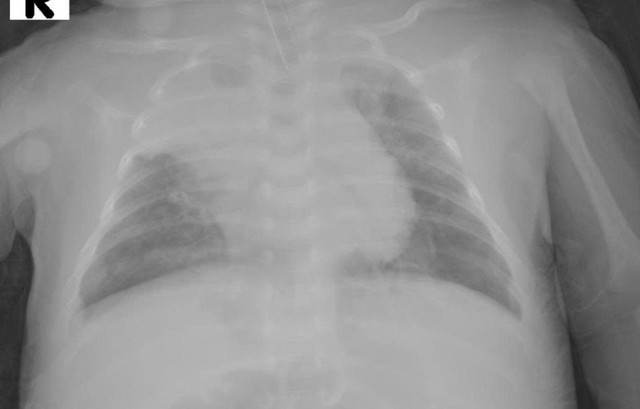

Đến cuối ngày thứ 3, bé suy hô hấp nặng, phải đặt ống nội khí quản và thở máy xâm nhập. Tuy nhiên phổi giãn nở kém, tổn thương lan tỏa, khí máu ghi nhận pH 7,1 và pCO₂ 115 mmHg, cho thấy toan hô hấp nặng.

Dù đã tối ưu các thông số thở máy thường, tình trạng vẫn không cải thiện, các bác sĩ quyết định chuyển sang thở máy tần số cao (High Frequency Oscillation – HFO), kỹ thuật hồi sức hô hấp hiện đại chỉ định cho các ca suy hô hấp nặng không đáp ứng với thở máy thông thường.

Sau 1,5 ngày thở HFO, phổi trẻ cải thiện rõ rệt, CO₂ giảm dần, khí máu ổn định. Bé được chuyển về thở máy thường theo chiến lược ARDS, cai máy thành công sau 7 ngày và ra viện khỏe mạnh sau hơn 15 ngày điều trị tích cực.